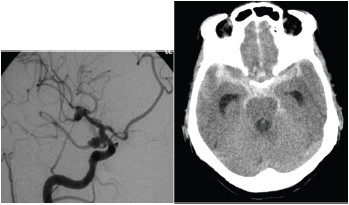

Considere uma paciente feminina, 59 anos, cefaleia inédita súbita de forte intensidade apresentando sonolência com pronto despertar, respondendo adequadamente aos comandos verbais com os seguintes exames de imagens.

É correto afirmar que se trata de: